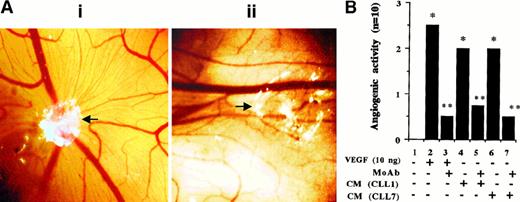

VEGF produced by CLL cells enhances angiogenesis. To test whether CLL-cell–secreted VEGF affects in vivo angiogenesis, the CAM assay was used with angiogenesis by rhVEGF 121 as a positive control. Results were assessed visually (Figure6A) and measured semiquantitatively (Figure 6B), as described in “Materials and methods.” The rhVEGF 121 induced a strong angiogenic response that was neutralized by an anti-hVEGF neutralizing antibody. CLL-cell–derived CM induced moderate angiogenesis that was also prevented by the neutralizing anti-hVEGF antibody. This indicates that CLL-cell–derived CM does have angiogenic activity and that VEGF contained in these supernatants is the major angiogenic factor.

Angiogenic responses of CAM to CM derived from CLL cells.

(A) Representative angiogenic response and its inhibition by a blocking anti-hVEGF mAb. The white area represents the site of application of filters containing either CM (collected from the PMA-stimulated cells) alone (i) or the same CM preincubated with anti-hVEGF MoAb for 2 hours at RT (ii). Microvessels radiating from the site of sample application in (i) are not formed in the presence of the blocking mAb (ii). (Original magnification, × 8.) (B) The semiquantitative data obtained by using rhVEGF and CM collected from PMA-stimulated cells from 2 patients. The grading of the angiogenic response is described in “Materials and methods.” *P < .05 vs control andP < .05 vs sample without the neutralizing antibody (Mann-Whitney U test). Each bar represents the score of 10 CAM used in 2 separate assays with similar results.